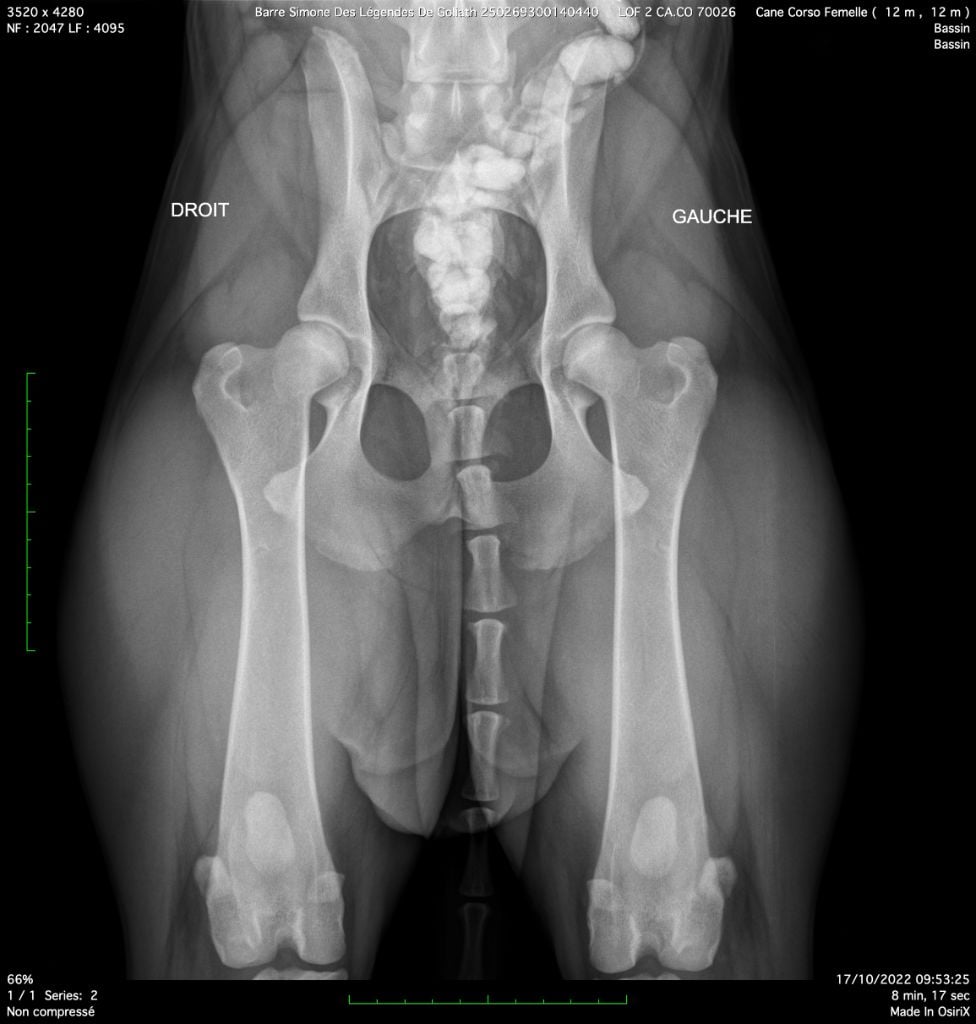

| Couleur | GRIS BRINGE DRSA N/N HD A / ED 0 officiel |